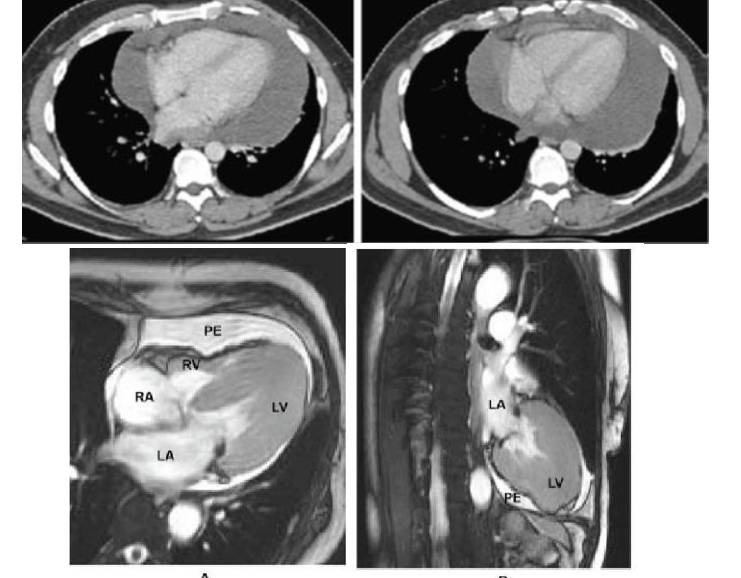

CT与MRI:可对积液的量及性质做出判定

♦1.少量积液:<100ml,舒张期心包厚度5-15mm,位于左室后壁及右房侧壁

♦2.中量积液:100-500ml,心包厚度15-24mm,位于右室前及心尖下外方

♦3.大量积液:>500ml,心包厚度>25mm,形成包绕心包的异常密度带

♦4.MR信号:炎性渗出含蛋白成分高—不均匀高信号

T1WI血性积液—中等或高信号

肿瘤—不均匀的混杂信号